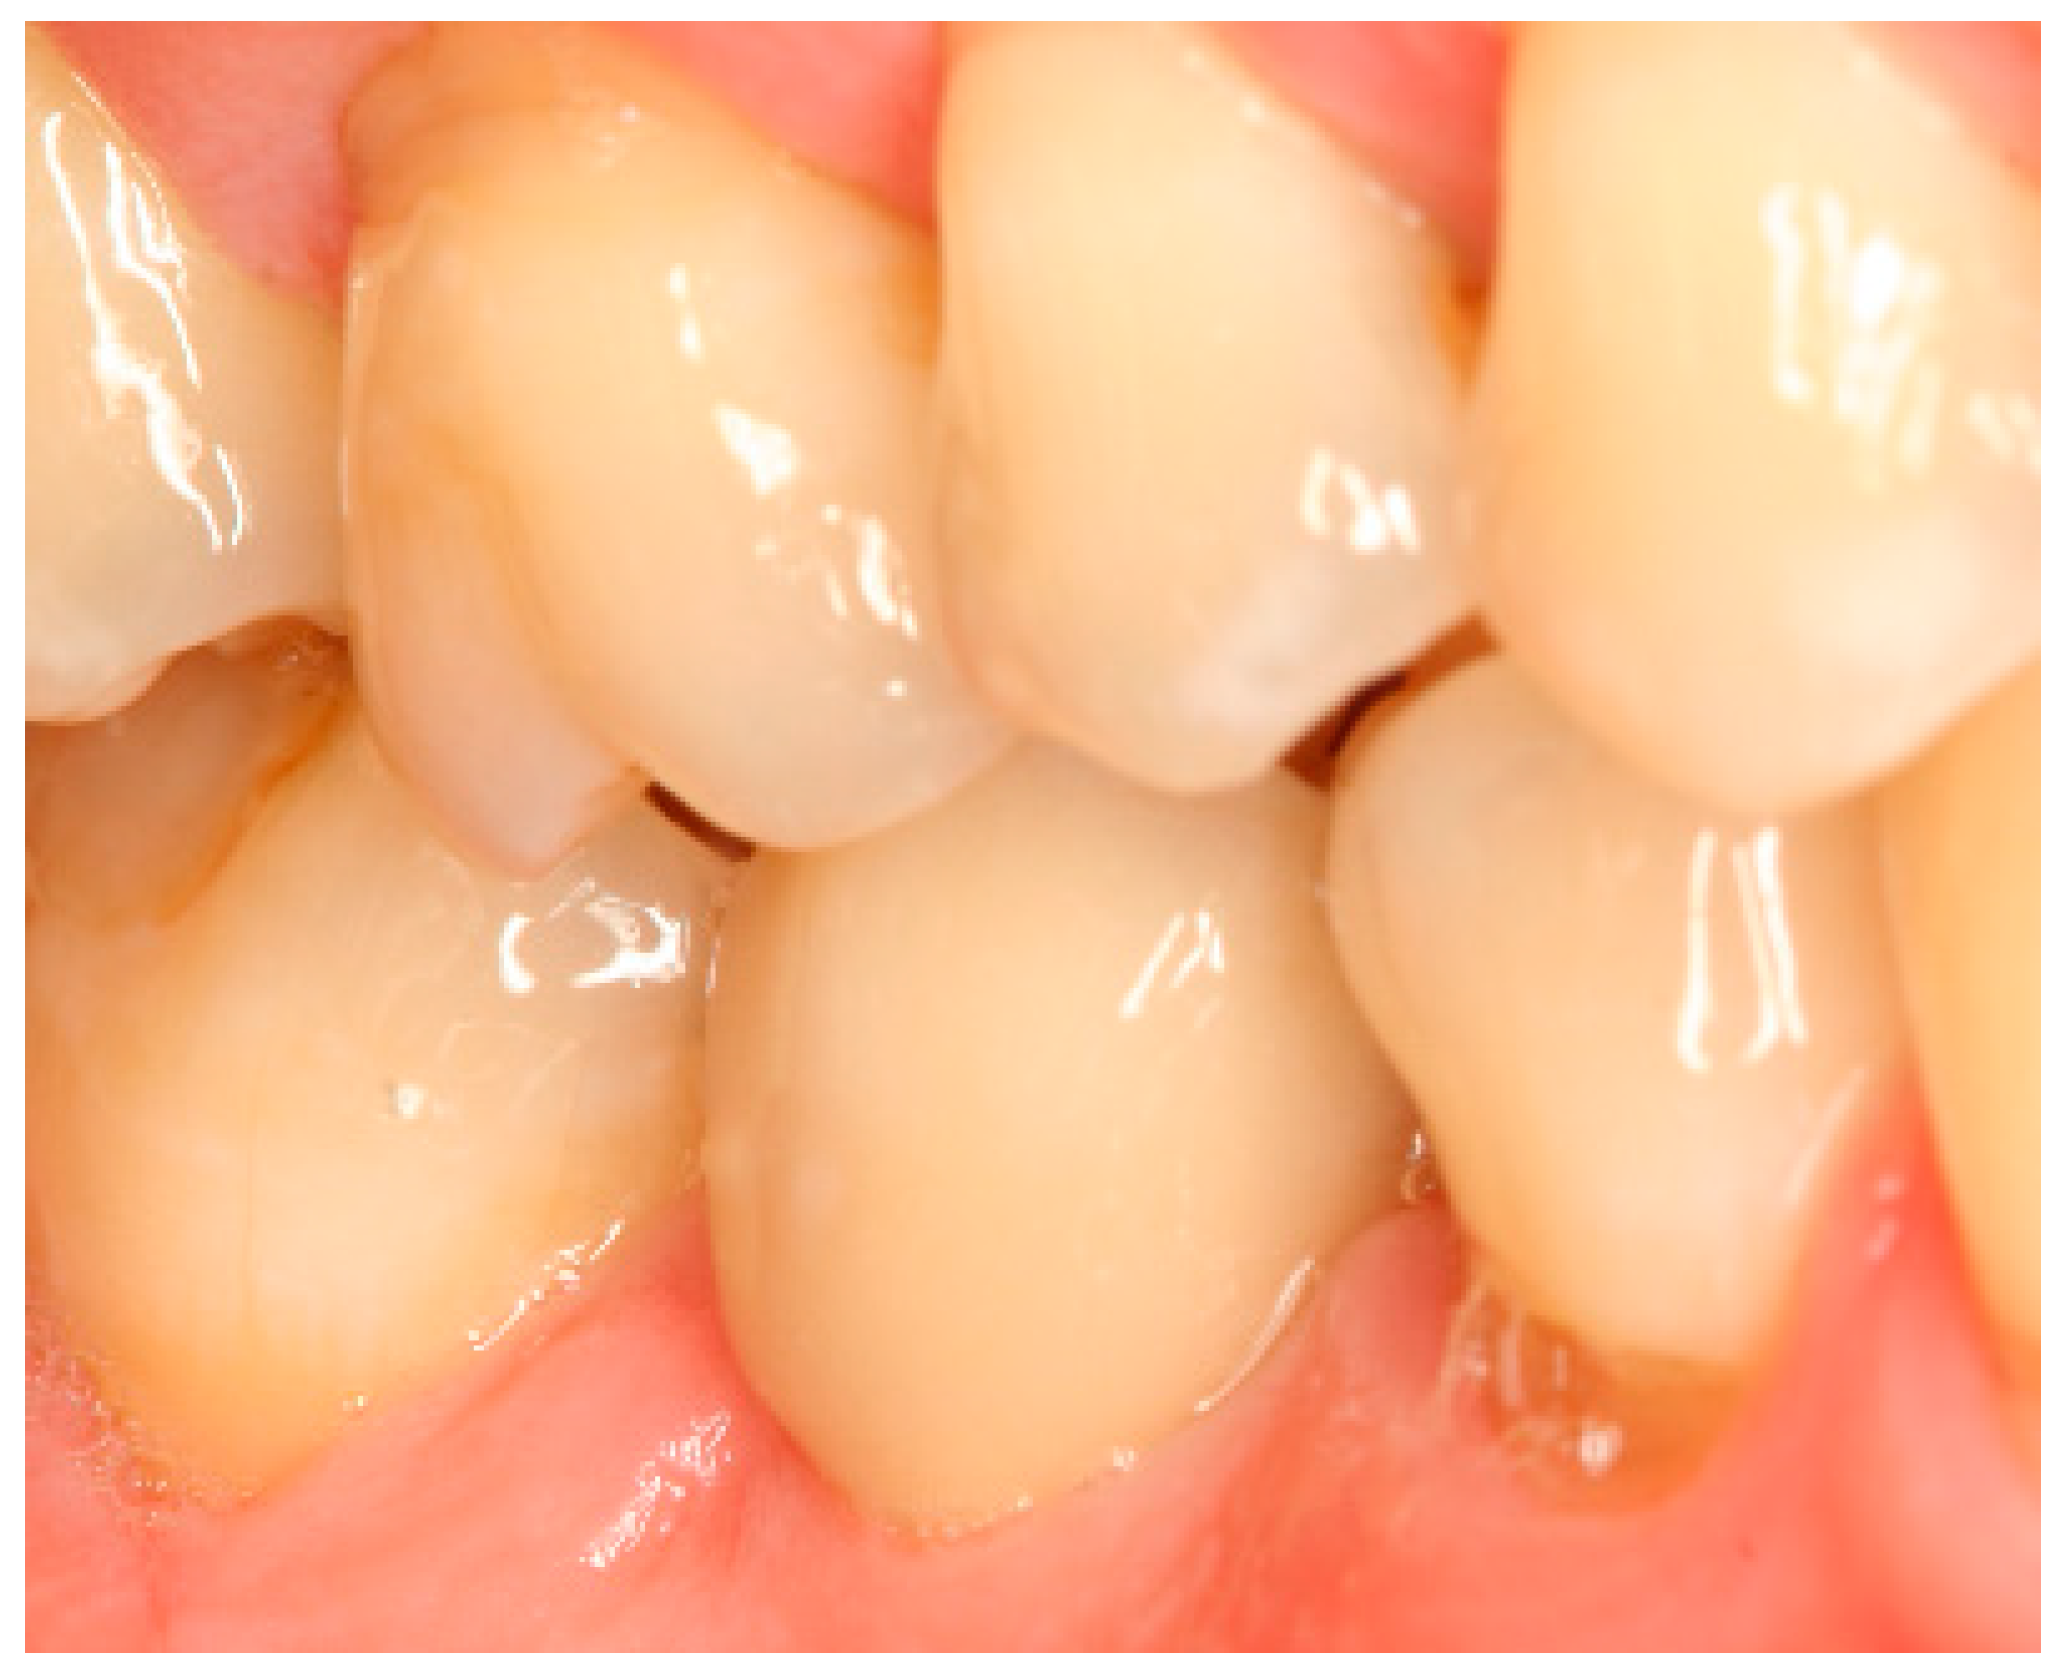

Situation after crown cementation. Lateral view.

Clinical situation at the 1-year follow-up. Lateral view.

Clinical situation at the 3-year follow-up. Lateral view.

Clinical situation at the 5-year follow-up. Lateral view.